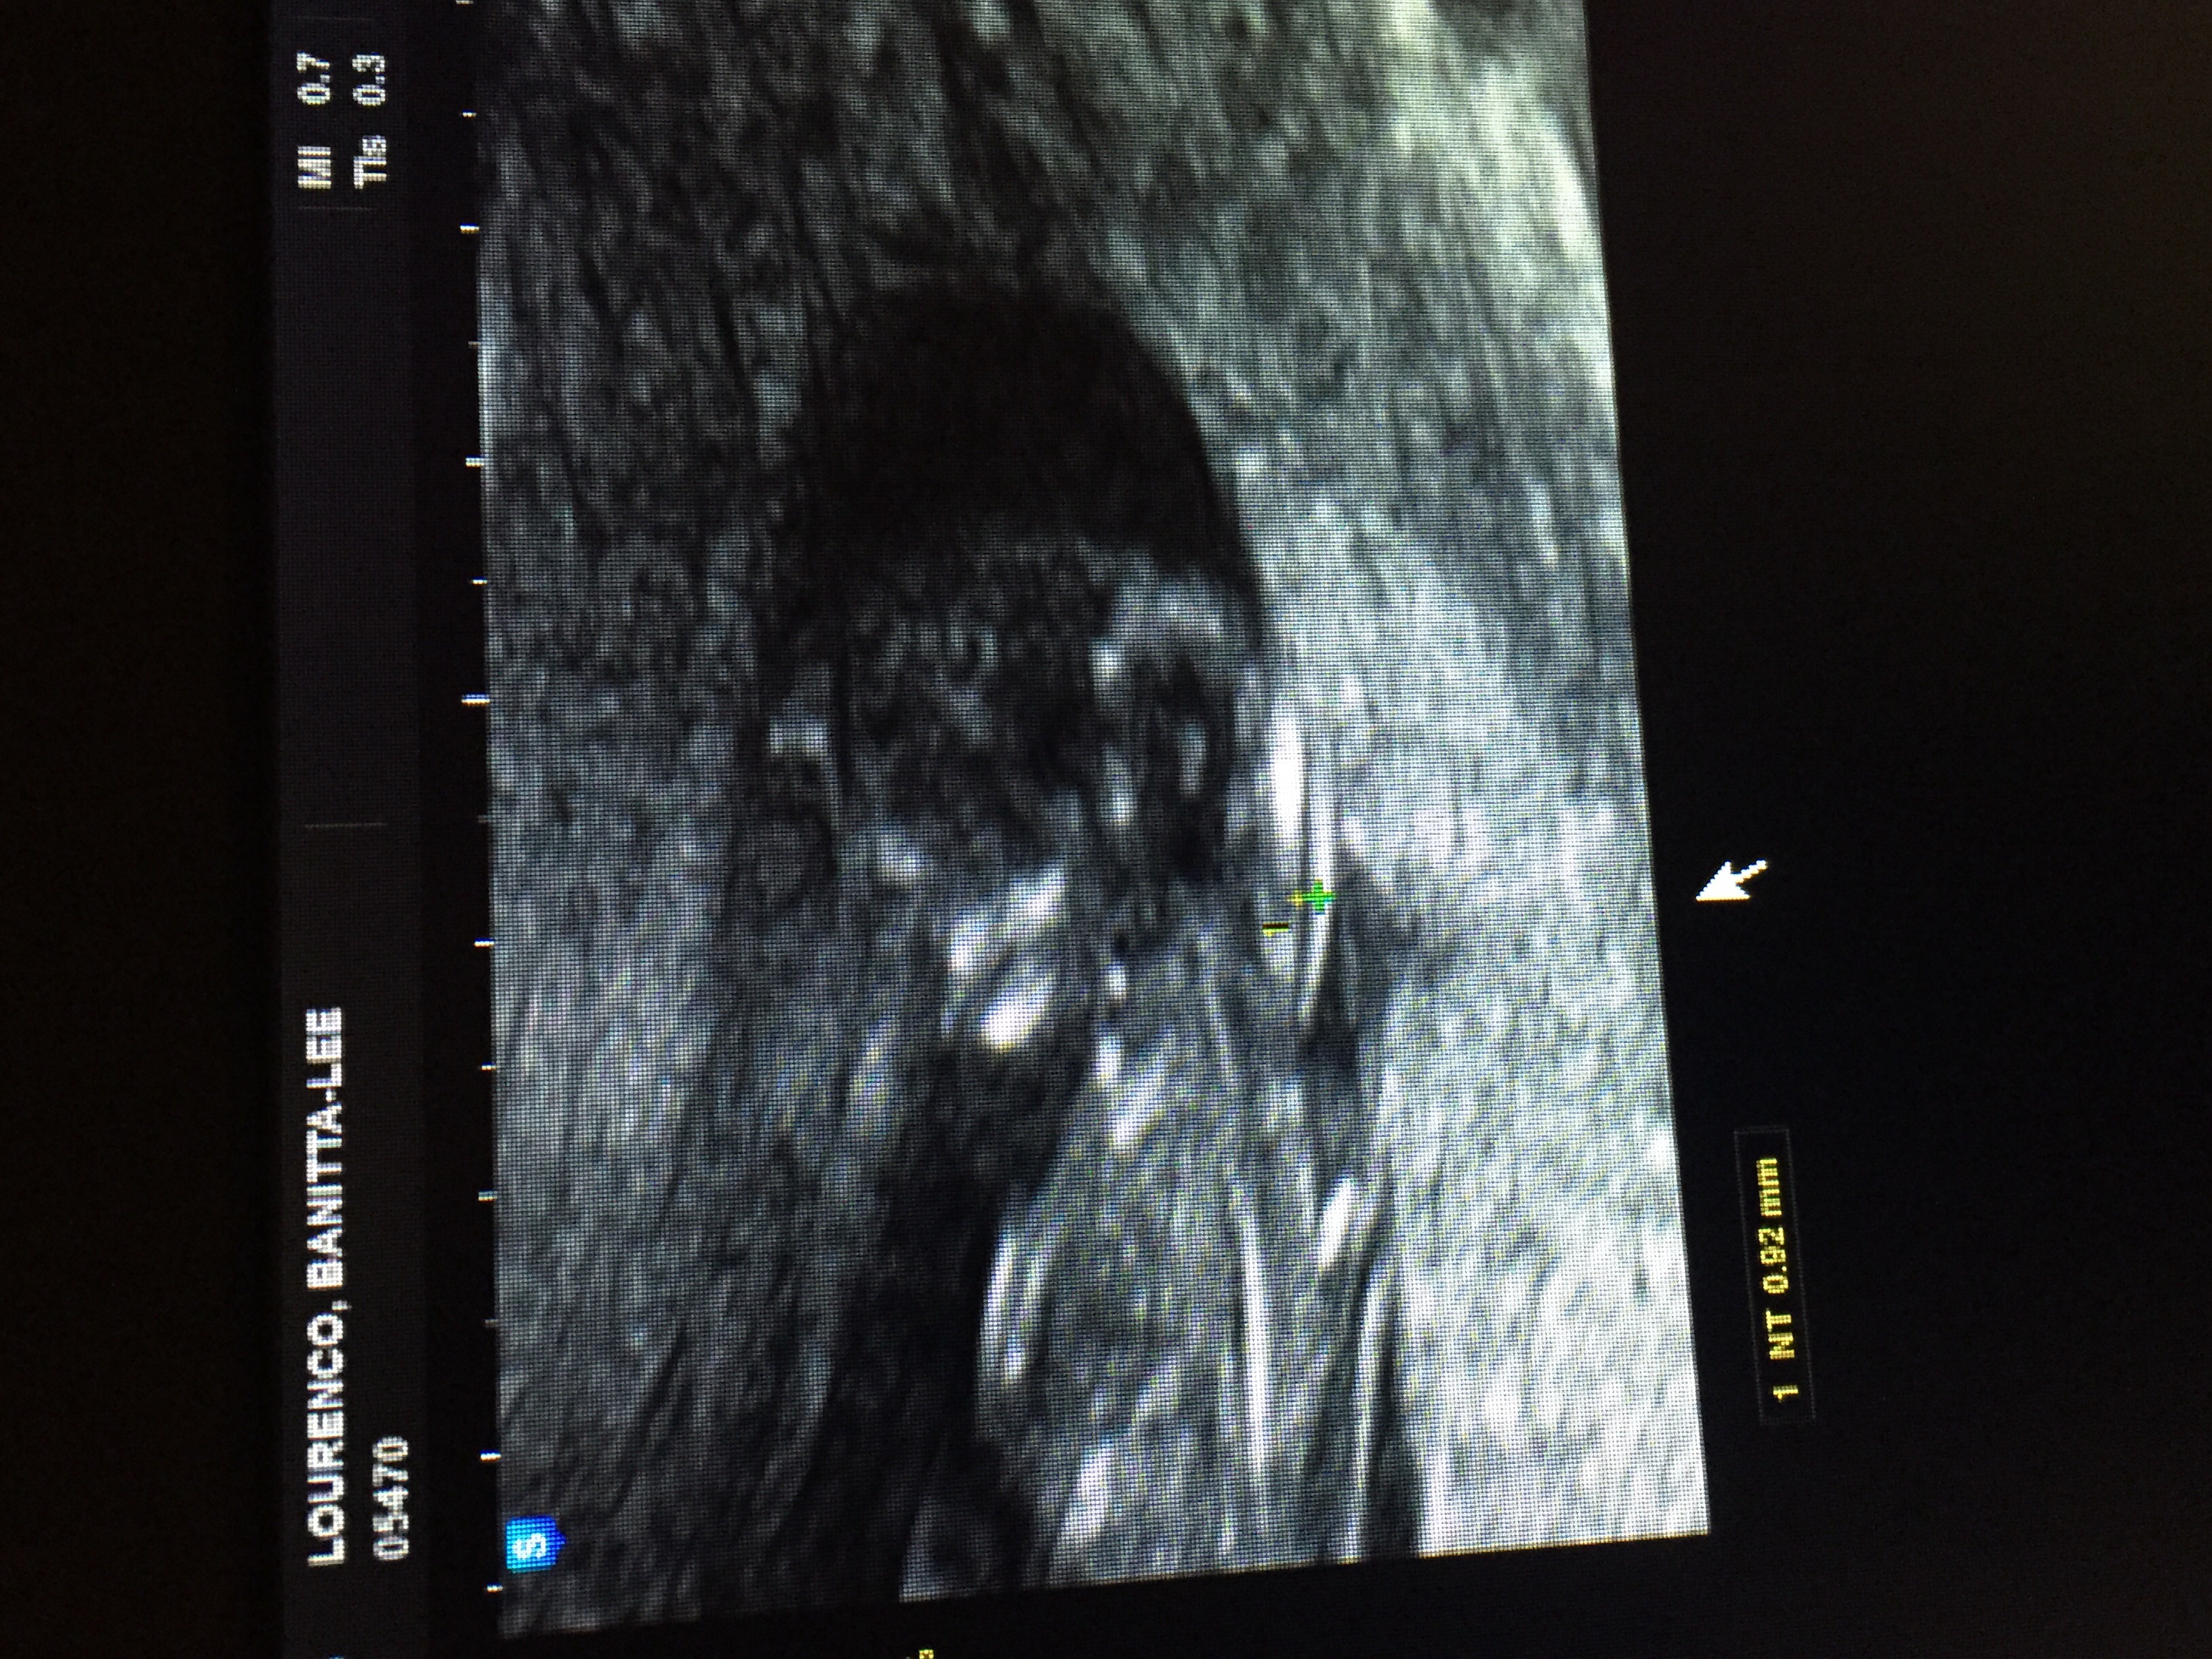

Woohoo!!! Based on my LMP I'm 12w4d and measured exactly 12w4d. HB was 140 and all when well with the NT scan. Big sighs of relief for this PGAL mama. Xo